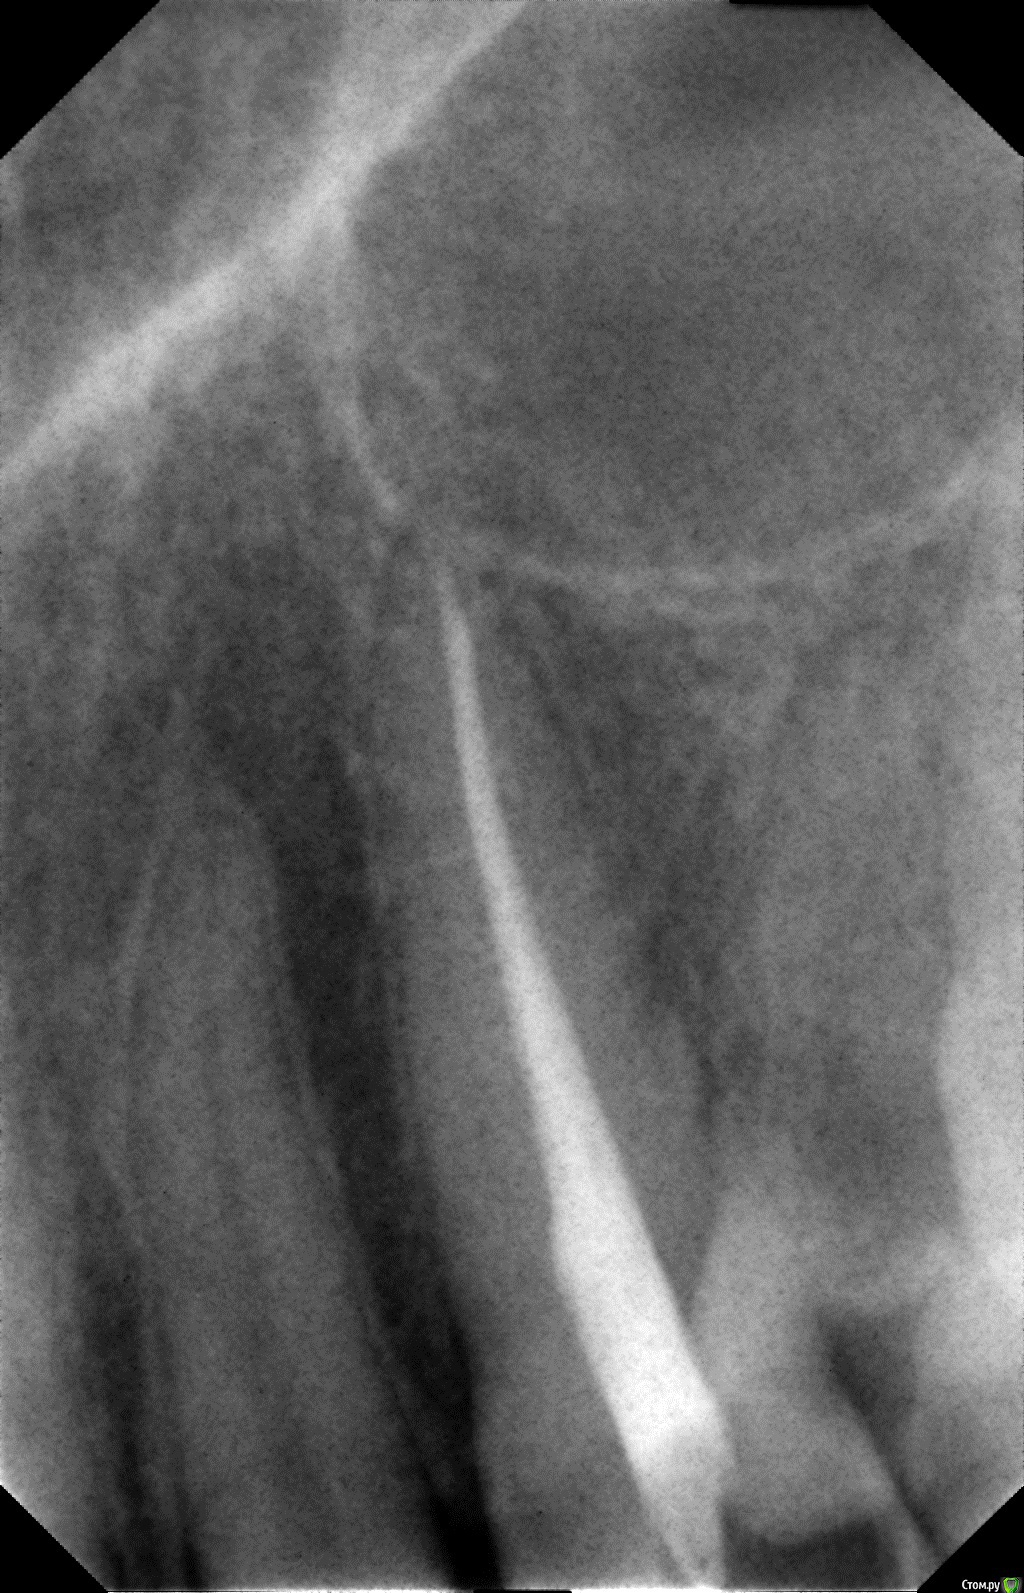

Jorus Опубликовано 27 октября, 2015 Поделиться Опубликовано 27 октября, 2015 (изменено) Добрый вечер уважаемые! Хочу спросить совета.1.Неделю назад был установлен титановый штифт (Radix Anker Standart)(желтый) на 23 зуб (клык), стоматолог не предупредила меня.Сам штифт видно из под пломбы с внутренней стороны. На кончике языка который соприкасается со штифтом есть постоянное жжение и не прекращающийся насморк. Возможна ли аллергия?Также штифт вместе с пломбой мешает прикусу и вся нагрузка левой челюсти приходится на клык, врач посоветовала спилить чу-чуть штифт! Можно ли обтачивать титановый штифт? 2. Как все было: обратился в клинику по поводу соседнего зуба, но сделав снимок врач обратила внимание на клык(23 зуб) и сказала что кариес скорей всего дошел до пульпы, но есть возможность его спасти.(50 на 50 как она сказала)! согласился на лечение зуба чтобы его сохранить( сейчас понимаю что сильно поспешил, нужно было идти в дорогую клинику, не к первому попавшемуся врачу и лечить под микроскопом.)В итоге лечения врач сказала что кариес слишком глубокий и спасти нерв не удалось (хотя думаю что она и не старалась его спасти)! 3. После депульпации в спешке (врач явно спешила то домой то еще кудато) запломбировала канал простой пастой (не лотеральной конденсацией), сделала контрольный снимок, залепила временной пломбой и отправила домой сказав приходить через 2 недели. 4.Все 2 недели зуб откровенно ныл (боль снимал зубными каплями на основе валерианки). Спустя 2 недели мучений пришел на прием, врач спросила ну что доделываем? я ответил утвердительно (предполагал что все закончится установкой световой пломбы и ничего уже испортить нельзя, смирившись с потерей нерва зуба)... но что произошло дальше.. 5.В конце "лечения" врач заявила мне, что она "укрепила" мой зуб титановым штифтом. Закрепила она его цементом ФУДЖИ. Придя домой погуглил в интернете про анкерные штифты и не найдя ни одного положительного отзыва впал в депрессию.. как я понимаю показаний для установки штифта не было! Работа сделана по принципу "и так сойдет".. 6.Знаю что сам виноват, что не ознакомился с планом лечения и не спросил доктора что она собирается делать=( Что посоветуете делать? На лечение потрачено 7500р.. Очень смущает второй снимок со штифтом Вопрос:1) Нормально ли запломбирован канал пастой? (первый снимок)2) Правильно ли установлен сам штифт? (второй снимок)3) Стоит ли извлекать штифт, чтобы в последствии не сломался корень зуба из-за "укрепления" штифтом?4) Если будет сохраняться аллергия есть ли смысл его удалять?5) Насколько это травматичная процедура по извлечению штифта? много ли здоровых тканей я потеряю? Не потеряю я зуб в процессе удаления штифта? Заранее благодарю! Тема очень важная для меня, не могу не спать, не есть нормально уже неделю изза вышеизложенного! Изменено 27 октября, 2015 пользователем Jorus Ссылка на комментарий

St. Опубликовано 27 октября, 2015 Поделиться Опубликовано 27 октября, 2015 1) Нормально ли запломбирован канал пастой? (первый снимок) 2) Правильно ли установлен сам штифт? (второй снимок) 3) Стоит ли извлекать штифт, чтобы в последствии не сломался корень зуба из-за "укрепления" штифтом? 4) Если будет сохраняться аллергия есть ли смысл его удалять? Снимок красивый конечно, но это увы не показатель качества в случае пломбировки канала одной пастой.Штифт я бы рекомендовала достать, поскольку если он контактирует с полостью рта - это плохо, и канал перепломбировать. Насколько это травматичная процедура по извлечению штифта? много ли здоровых тканей я потеряю? Не потеряю я зуб в процессе удаления штифта? Процедура нетравматичная. Риски минимальные. 1 Ссылка на комментарий

Гарриевич Опубликовано 28 октября, 2015 Поделиться Опубликовано 28 октября, 2015 Штифт желательно удалить? и перепломбировать канал? Вы так считаете? даработа не сложная 1 Ссылка на комментарий

St. Опубликовано 28 октября, 2015 Поделиться Опубликовано 28 октября, 2015 Перепломбировать по причине того что канал запломбирован одной пастой? Сложно ли будет канал перепломбировать и каким методом желательно? Да. Несложно. Запломбировать гуттаперчей с эпоксидным силлером, методика не принципиальна. Ссылка на комментарий